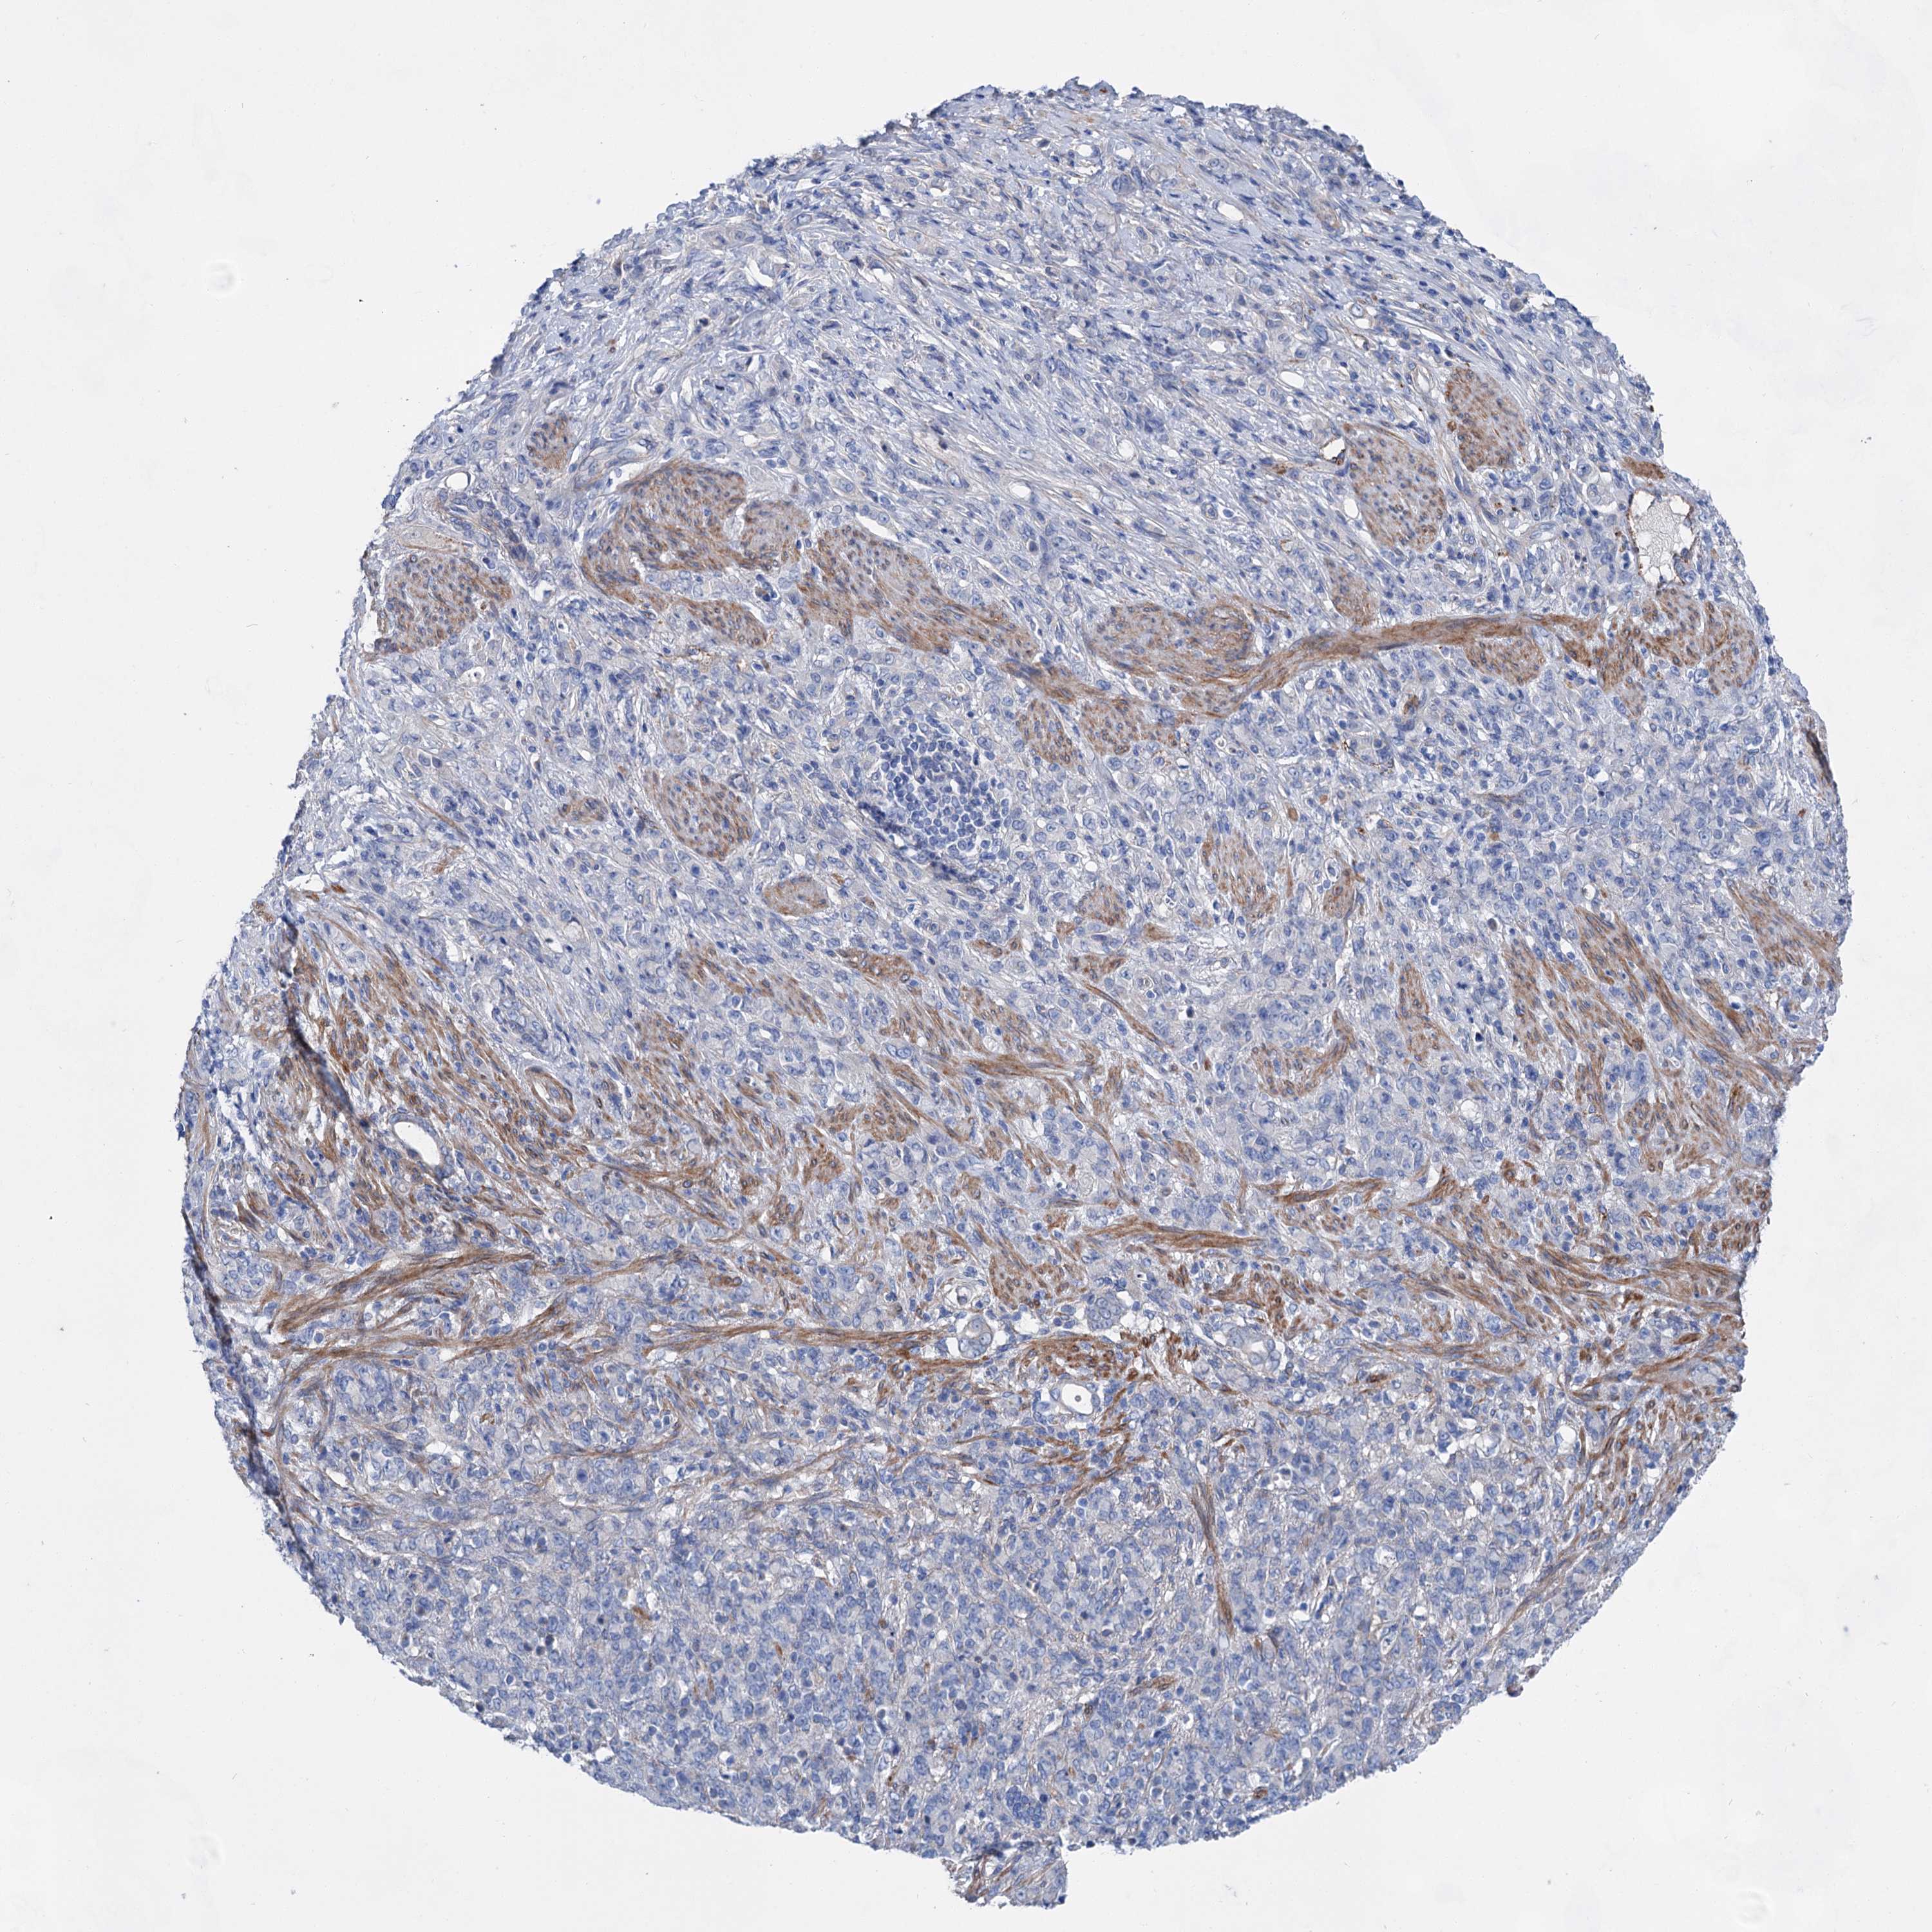

STOMACH CANCER - Protein expressioni

A mouse-over function shows sample information and annotation data. Click on an image to view it in a full screen mode. Samples can be filtered based on level of antibody staining by selecting one or several of the following categories: high, medium, low and not detected. The assay and annotation is described here.

Note that samples used for immunohistochemistry by the Human Protein Atlas do not correspond to samples in the TCGA dataset.

Antibody stainingi

Antibody staining in the annotated cell types in the current human tissue is reported as not detected, low, medium, or high, based on conventional immunohistochemistry profiling in selected tissues. This score is based on the combination of the staining intensity and fraction of stained cells.

Each image is clickable and will lead to virtual microscopy that enables deeper exploration of all samples and also displays staining intensity scores, fraction scores and subcellular localization as well as patient and tissue information for each sample.

Antibody HPA036159

Antibody HPA057384

Staining

High

Medium

Low

Not detected

Intensity

Strong

Moderate

Weak

Negative

Quantity

>75%

75%-25%

<25%

None

Location

Nuclear

Cytoplasmic/membranous

Cytoplasmic/membranous,nuclear

Adenocarcinoma, NOS

Adenocarcinoma, High grade